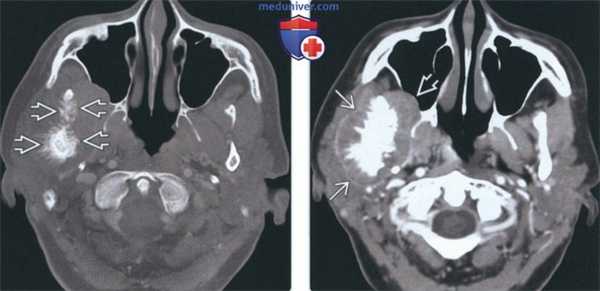

(Слева) На аксиальной КТ в костном окне на уровне сигмовидной вырезки справа визуализируется остеосаркома ветви и мыщелка нижней челюсти. Кортикальные пластинки утолщены, определяется лучистая периостальная реакция вокруг пораженных участков кости. Обратите внимание на асимметричный отек мягких тканей жевательного пространства и щеки справа.

(Справа) На аксиальной КТ с КУ у этого же пациента визуализируется опухоль, смещающая околоушную железу кзади и кнаружи, и вероятно, прорастающая в нее. Опухоль распространяется в правую верхнечелюстную пазуху.

(Слева) На аксиальной КТ в костном окне визуализируется большая агрессивная остеосаркома со стороны наружного края ветви нижней челюсти. Определяется лучистая периостальная реакция, виден остеоидный матрикс.

(Справа) На корональной КТ в костном окне у этого же пациента определяется лучистая периостальная реакция со стороны внутреннего и наружного края ветви с «пятнистой» деструкцией и увеличением мыщелка.